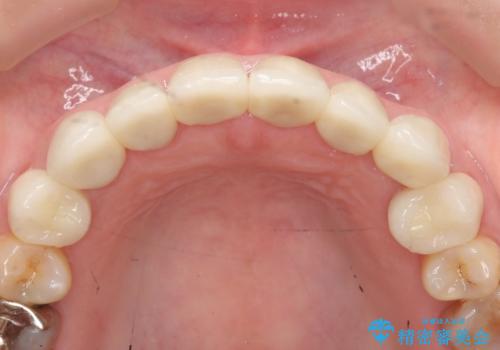

- 上下顎前歯部の見た目が気になるといらっしゃった方の症例です。

上顎は左4番から右4番までの8歯、下顎は左3番から右3番までの6歯、計14歯をオールセラミッククラウンにより補綴しました。